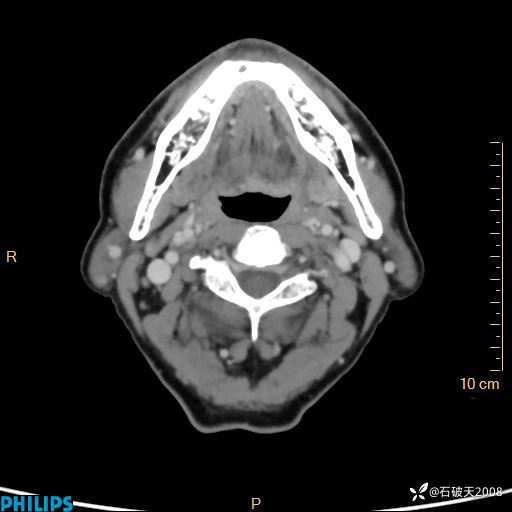

病例分享:老年男性,颈部占位,一周后公布病理

胡志勇HZY 达人已点赞男 61岁 主 诉:发现左侧面部肿物1年余。

现病史:患者于1年余前无意间发现左侧耳下有一肿物,大小如“花生米样”,无压痛,无明显红肿,无畏寒、发热,无咳嗽、咳痰,无盗汗、心慌,无手足颤动、胸闷及性格改变,未在意,未给予特殊处理,2天前至我院行彩超示: 左侧腮腺内低回声(考虑肿大淋巴结),现患者为求进一步诊治,遂来我院就诊,门诊以“局部肿物”为诊断收住我科。自发病来,患者神志清,精神可,饮食睡眠尚可,大小便正常,近期体重无下降。

静脉期